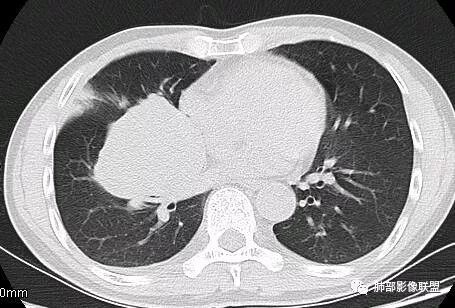

这一个类圆形,边界光滑,明显膨胀生长为主,如果起源中叶支气管,按理中叶支气管不动,固定在中叶支气管上,推移其他结构

但是现在的片显示,其主体在下叶,中叶支气管壁由下朝上有推移

南边:就不符合这个原理

初学者:如果中叶病灶,叶间裂应该下推,也不会上推

而且支气管內密度较高是粘液栓,远端支气管也是通畅,所以支气管内是因为受压所以痰液引流不畅。

南边:从叶裂的变形,下朝上,越来越朝前扭曲,提示叶裂局部有朝前上推移的趋势

南边:下叶的支气管受压后移、变形

南边:病灶边界清,提示侵袭性弱,膨胀生长为主;这时候我们提示病灶不应该是支气管关系密切,提示间叶来源或胸膜来源